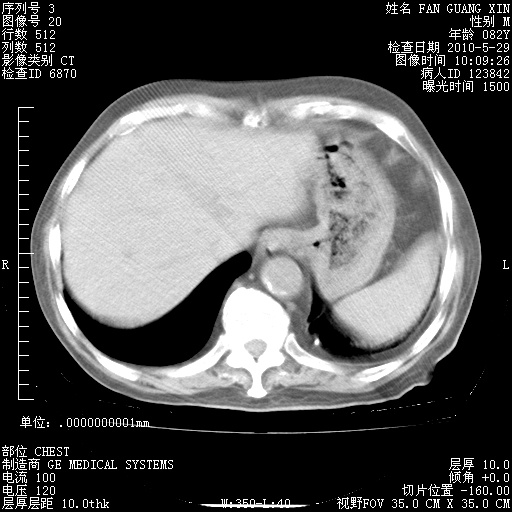

再治疗10天后的肺部CT

阅读此次胸部CT,肺间质渗出性改变较入院时有吸收。目前从体温、白细胞、中性分叶明显增高,肯定存在细菌感染(发生医院感染哦,若无消化道及泌尿系统等感染的依据,肺部感染可能大)。若你院头孢哌酮舒巴坦钠耐药率较高,同意你的方案,若48小时体温仍高,可考虑使用碳青霉稀类抗菌药物,同时可予超声雾化、注意滴数时加大液体量。白蛋白33.30g/L较低哦,需加强营养等支持治疗。